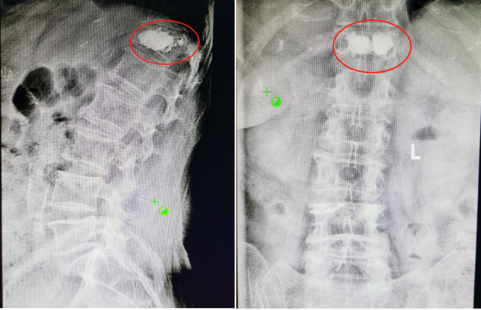

在李奶奶和家属同意进行手术后,陕西冶金医院神经脊柱科熊东主任为她成功进行了胸12椎体压缩性骨折。手术后当天,李奶奶的腰背痛就出现了明显缓解,术后第二天就可以下地活动行走。

术后影像学资料: